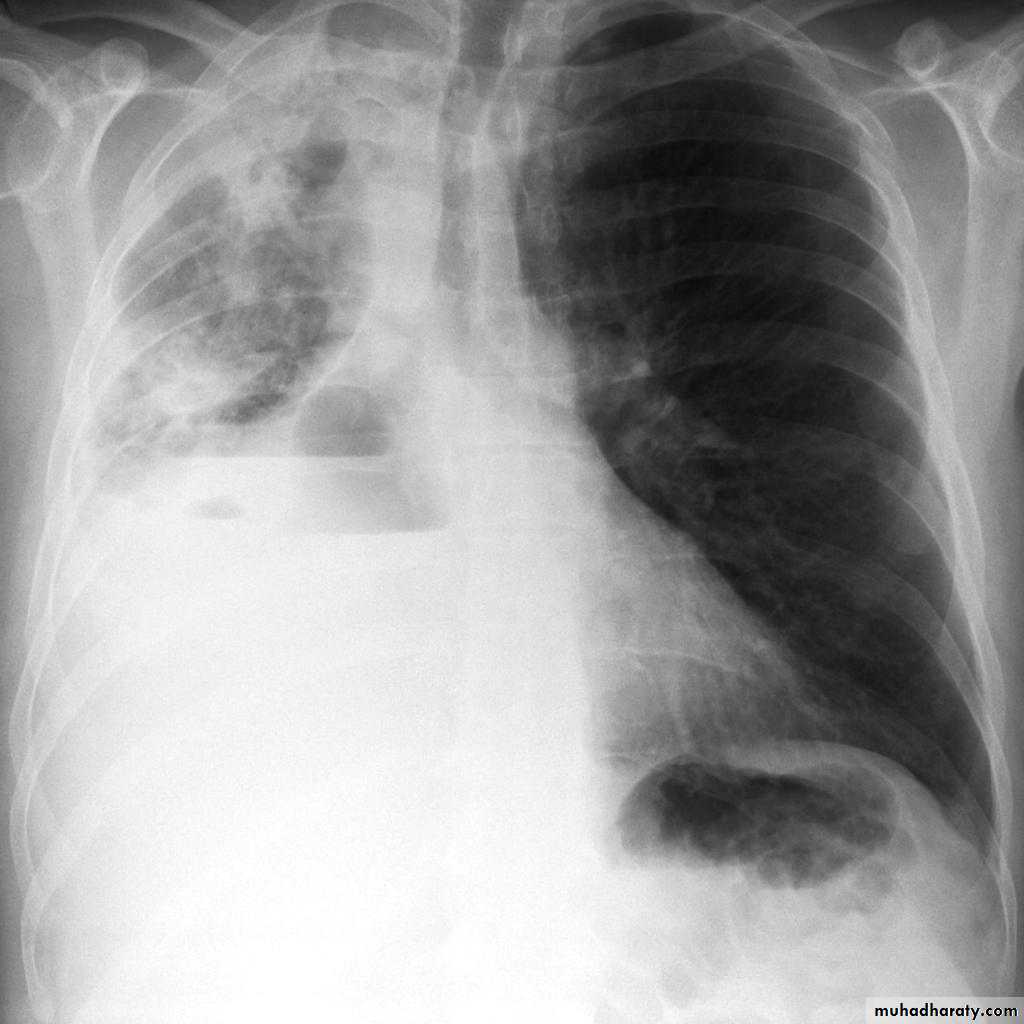

Unilateral obstructive emphysemaunilateral emphysema or atelectasis are the most common findings; only uncommonly will a radio-opaque foreign body be demonstrated ,Aspirated foreign bodies have a predominance for the right tracheo bronchial tree.